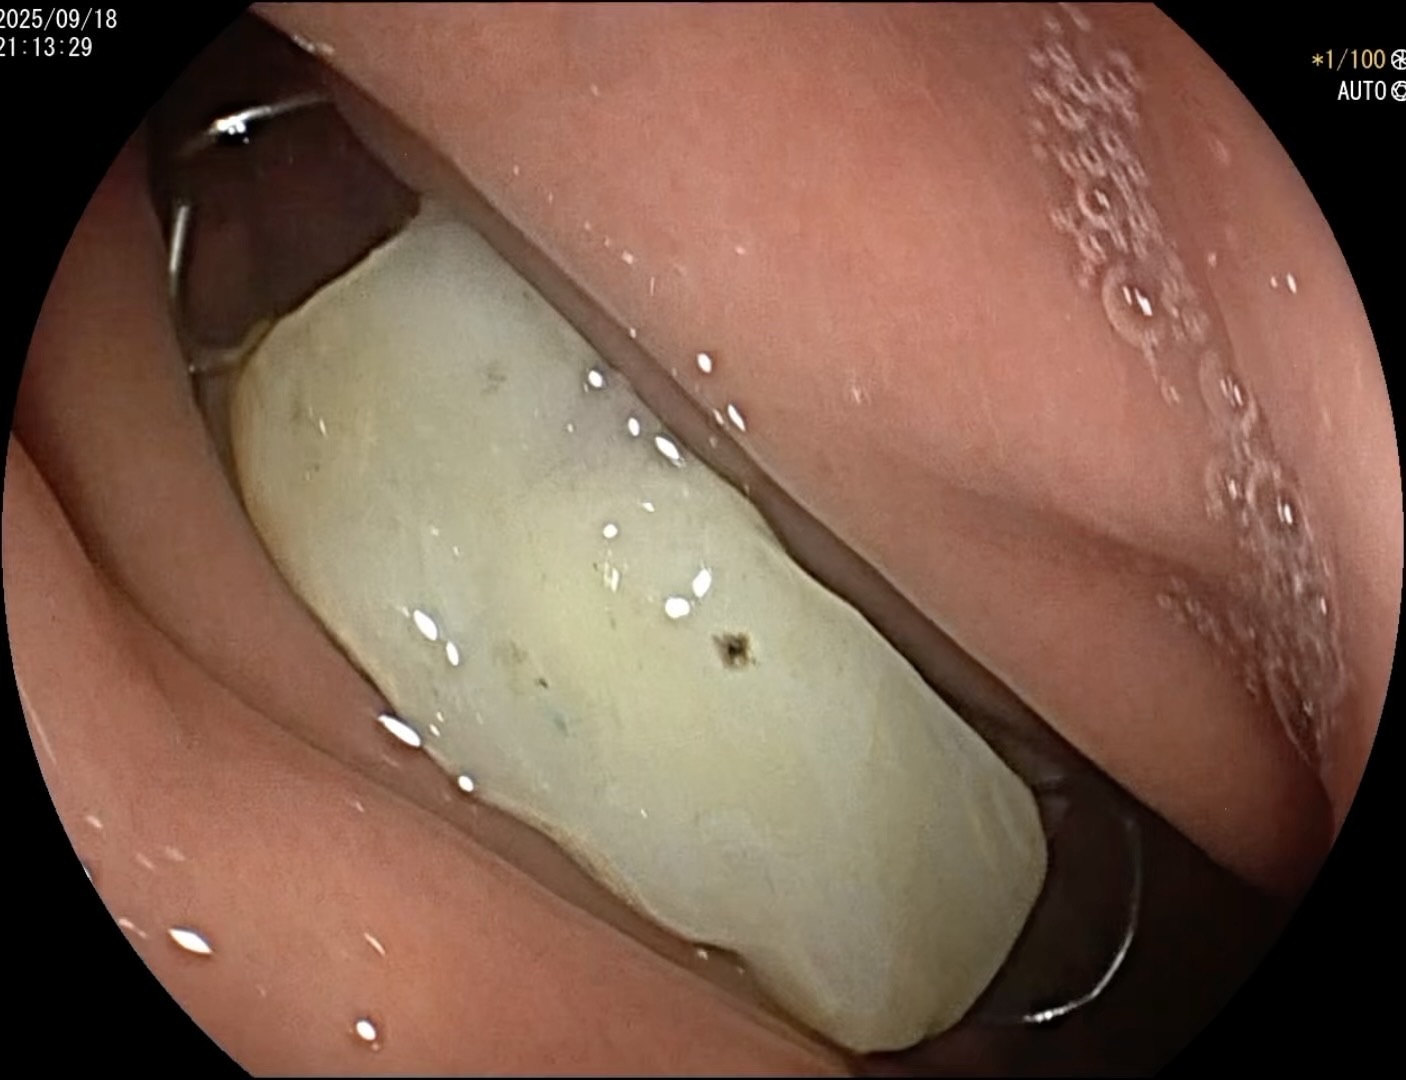

内镜进去发现和我们片子看到的有所不同,正好钩子向内,周围圆滑,经内镜下可以直接取出,安全套没有派上用场,但胃镜室很有必要备类似的保护罩。